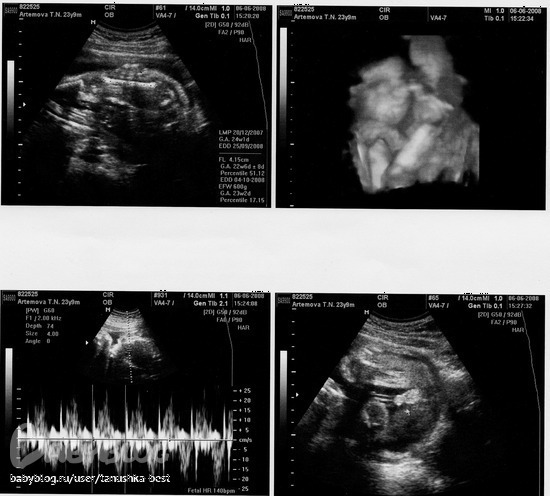

23 недели, щекастик такой =)